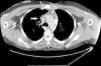

Physical examination revealed facial oedema, dilated neck veins and an increase in the number of collateral veins in the upper thorax, shoulder and right arm. Mediastinal widening and bilateral subpulmonary pleural effusion were observed on the chest radiograph. Chest computed tomography (CT) showed a widened mediastinum with fat trabeculation which caused a mass effect affecting the superior vena cava (Fig. 1). The 3D angiographic reconstruction showed an extensive network of collateral circulation due to obstruction of the superior vena cava that extended towards the chest wall, upper limbs and abdomen (Fig. 2). No thrombi were observed in the vena cava. Based on these findings, a diagnosis of SVCS was made. A phlebography was performed to assess the vascular involvement and to place an endovascular stent in order to re-permeabilise the venous circulation. However, this treatment was unsuccessful due to total obstruction of the subclavian veins, which made it difficult to access the vena cava. In view of the obstruction of the superior vena cava by a mediastinal infiltrative process, a mediastinotomy was performed to determine its cause. The biopsy showed adipose tissue with little cellularity; no granulomas, calcifications or malignant cells were identified. The tuberculin test did not reveal induration, and the bronchoaspirate and biopsy material cultures for mycobacteria and fungi were negative. The patient was diagnosed with SVCS due to mediastinal fibrosis of idiopathic origin.